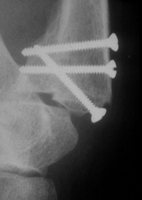

| Gelingt die geschlossene Repostion nicht, so muß

offen reponiert werden. Dies Verfahren aber ist besonders schwierig,

da das Fragment nicht ideal darstellbar ist. Auch in der Hand des

Erfahrenen ist nicht immer optimale stufenfreie Stellung erzielbar.